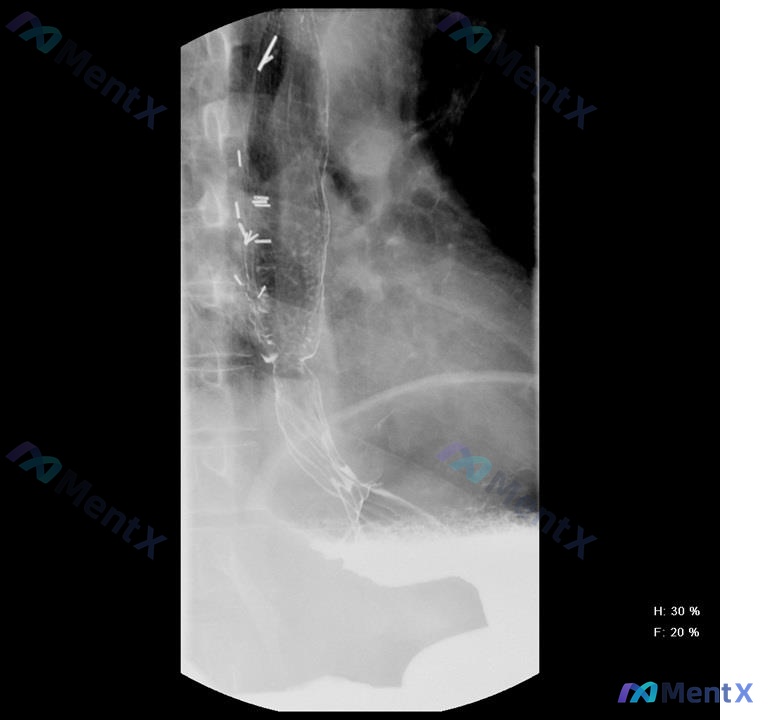

整理到一份食管钡餐造影的影像资料,先给几个核心的影像表现,附了几个常见的食管病变选项,大家第一眼会先往哪个方向靠? 影像核心表现: 1. 食管中上段管腔扩张,中下段可见一处明显狭窄 2. 食管内有明确的圆柱状网格结构影 3. 造影剂能通过网格结构向下,但到远端狭窄处通过明显变慢,呈细线状通过 4....